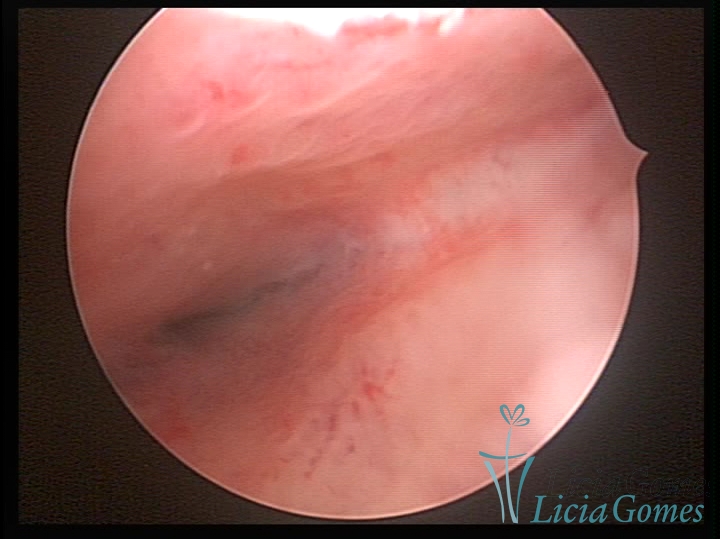

Unicornuate uterus

It presents a tubular cavity with an impaired intracavitary space, resembling the shape of a banana, whose the narrowest edge contains the tubal ostium. The endometrium is compatible with the menstrual cycle and the cervical canal is normal, in structure and trophism.